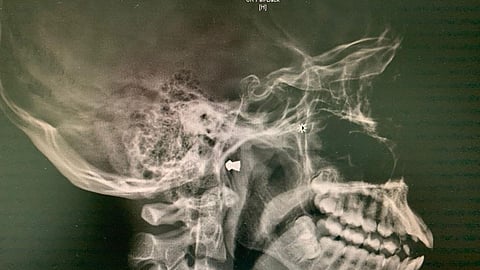

وأوضح الدكتور عاهد عقيل، استشاري جراحة الأنف والأذن والحنجرة الذي قام بإجراء العملية، اليوم الخميس، أن المصاب حضر لقسم الطوارئ إثر تعرضه لرصاصة وبعد إجراء الفحوصات والأشعة اللازمة تبين أن الرصاصة دخلت من أنفه إلى البلعوم الأنفي واستقرت بمحاذاة قاع الجمجمة.

وأشار إلى أنه تم إدخال المصاب لغرفة العمليات تحت التخدير العام وتكون الفريق من أخصائية الأنف والأذن والحنجرة الدكتورة بيان جان وطبيب التخدير الدكتور محمد حجازي، وتم استخراج الرصاصة بنجاح وتم خروج المصاب من المستشفى بعد ملاحظته وتحسن حالته الصحية دون أي مضاعفات.